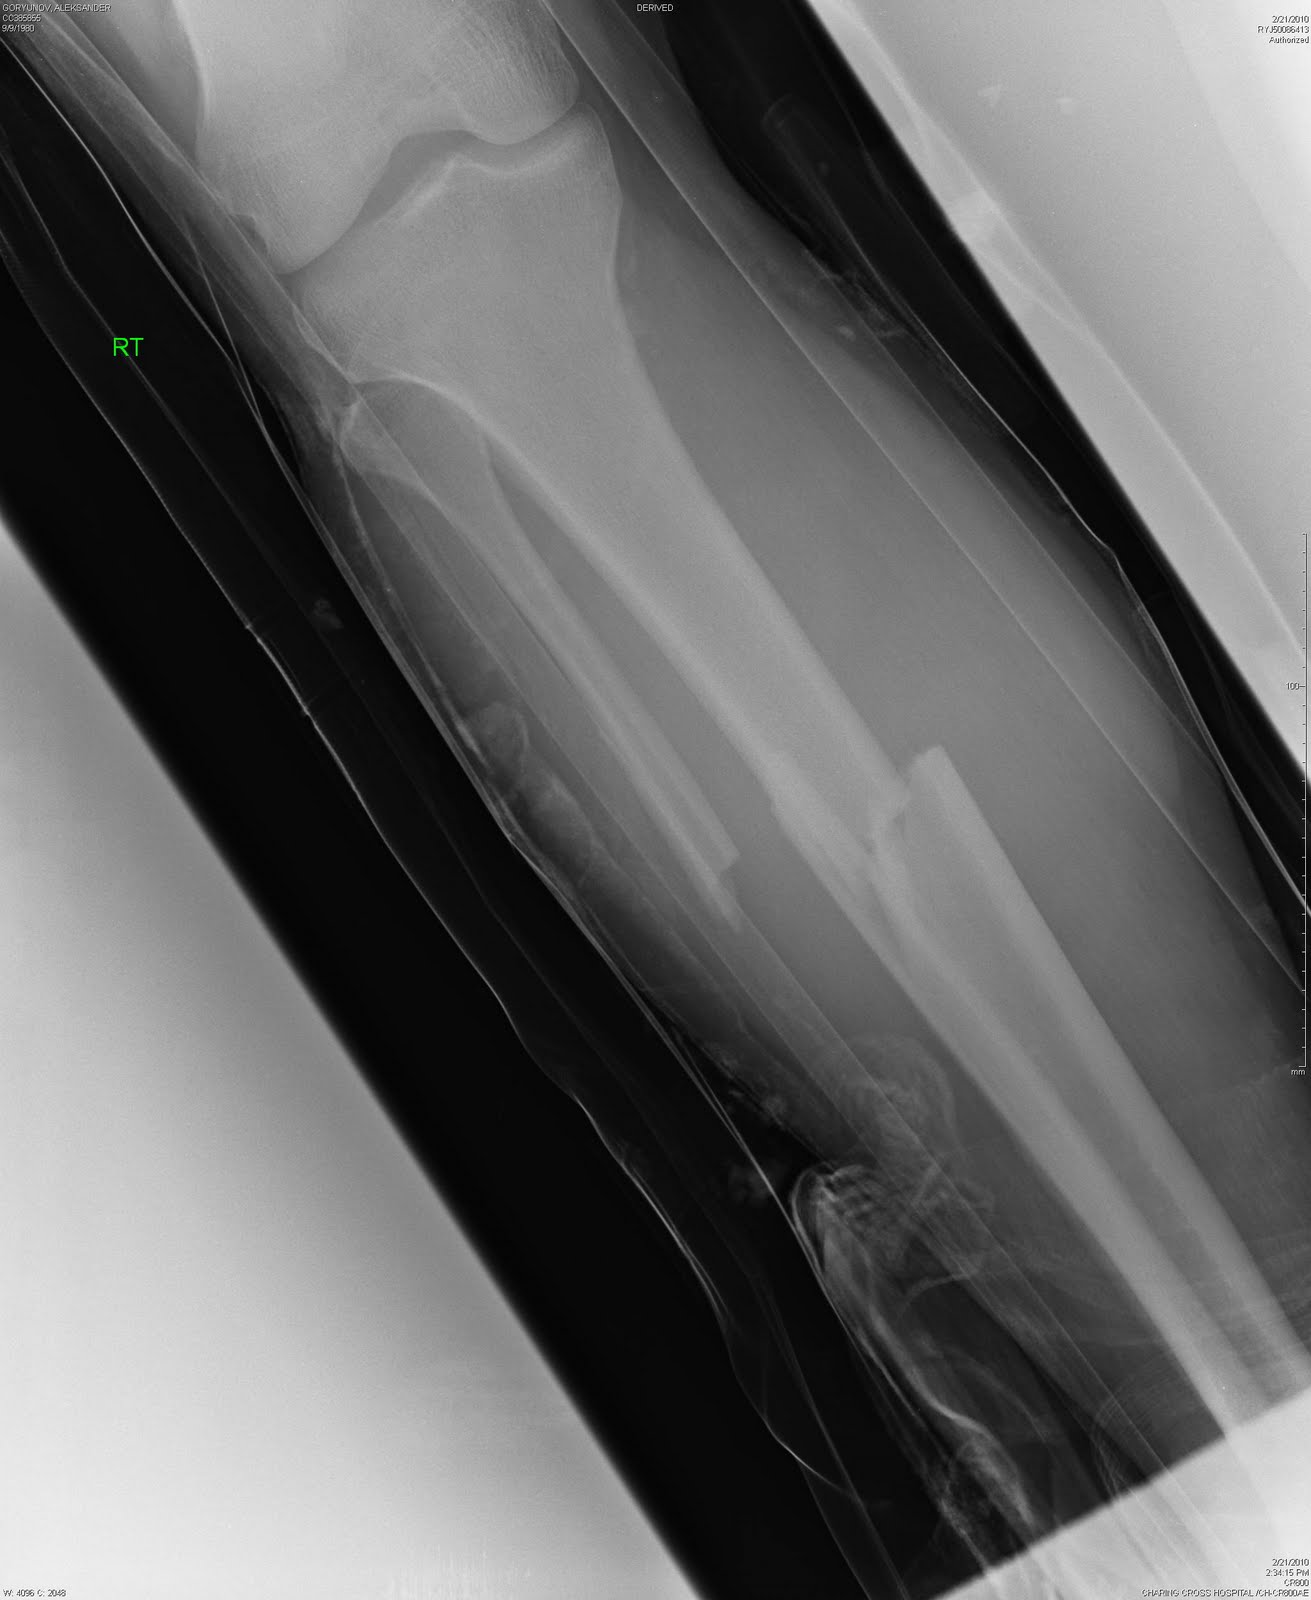

Перелом двойной - тибии и фибулы - закрытый, с клиновидным и сильно смещенным раздроблением тибии. Выглядит все это не очень, так что неудивительно, что мне он показан не был (увижу его только через месяц, когда на CD все рентгены пришлют домой).

Снимок еще раз подтвердил, что мне повезло - гетра с колготками (да, зимой иногда пододеваю к всеобщему смеху колготки - ноги в тепле, проблем с мышцами меньше) каким-то образом удержали ногу после сильнейшего удара и кость не пробилась наружу. Конечно, с другой стороны не повезло - сьехал щиток и оголил ногу в этом месте – но... бывает, а могло быть и хуже.

После изначального вправления, все это стало выглядеть вот так.

Ну, а во время операции под коленом внутрь кости вводят титановый стержень (длина - 40см, диаметр - 12 мм), который фиксируется парой винтов над лодыжкой и парой под коленом. Через год, весь этот металлолом можно вытащить обратно (что я и собираюсь сделать летом 2011-го). Операция нынче достаточно стандартная, только у меня немного осложненная выбитом на колени "клином", так что "ковырялись" в ноге не полтора часа, а три. Без гипса. С некоторыми деталями я уже был знаком - 2 года назад ошибся на выходе и сломал ногу нападающему. У него перелом был "чище" моего. А мне - карма. Результат вот такой.